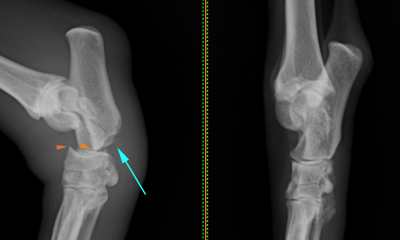

Web右後肢跛行を主訴に来院 50cm程の高さのソファーより飛び降りて受傷 右足根関節(かかと・踵)の腫脹、疼痛を認めました レントゲン検査にて踵骨(かかと)の骨折と診断しまし